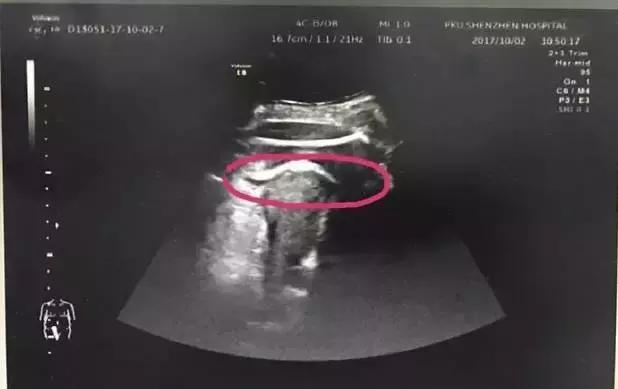

医生初步怀疑患者子宫破裂,当即安排做了B超。检查发现,胎儿的一条腿“踢破”了子宫,进入了腹腔,大腿根正卡在子宫壁上!

红色圆圈处是胎儿的腿,已经伸到子宫壁外